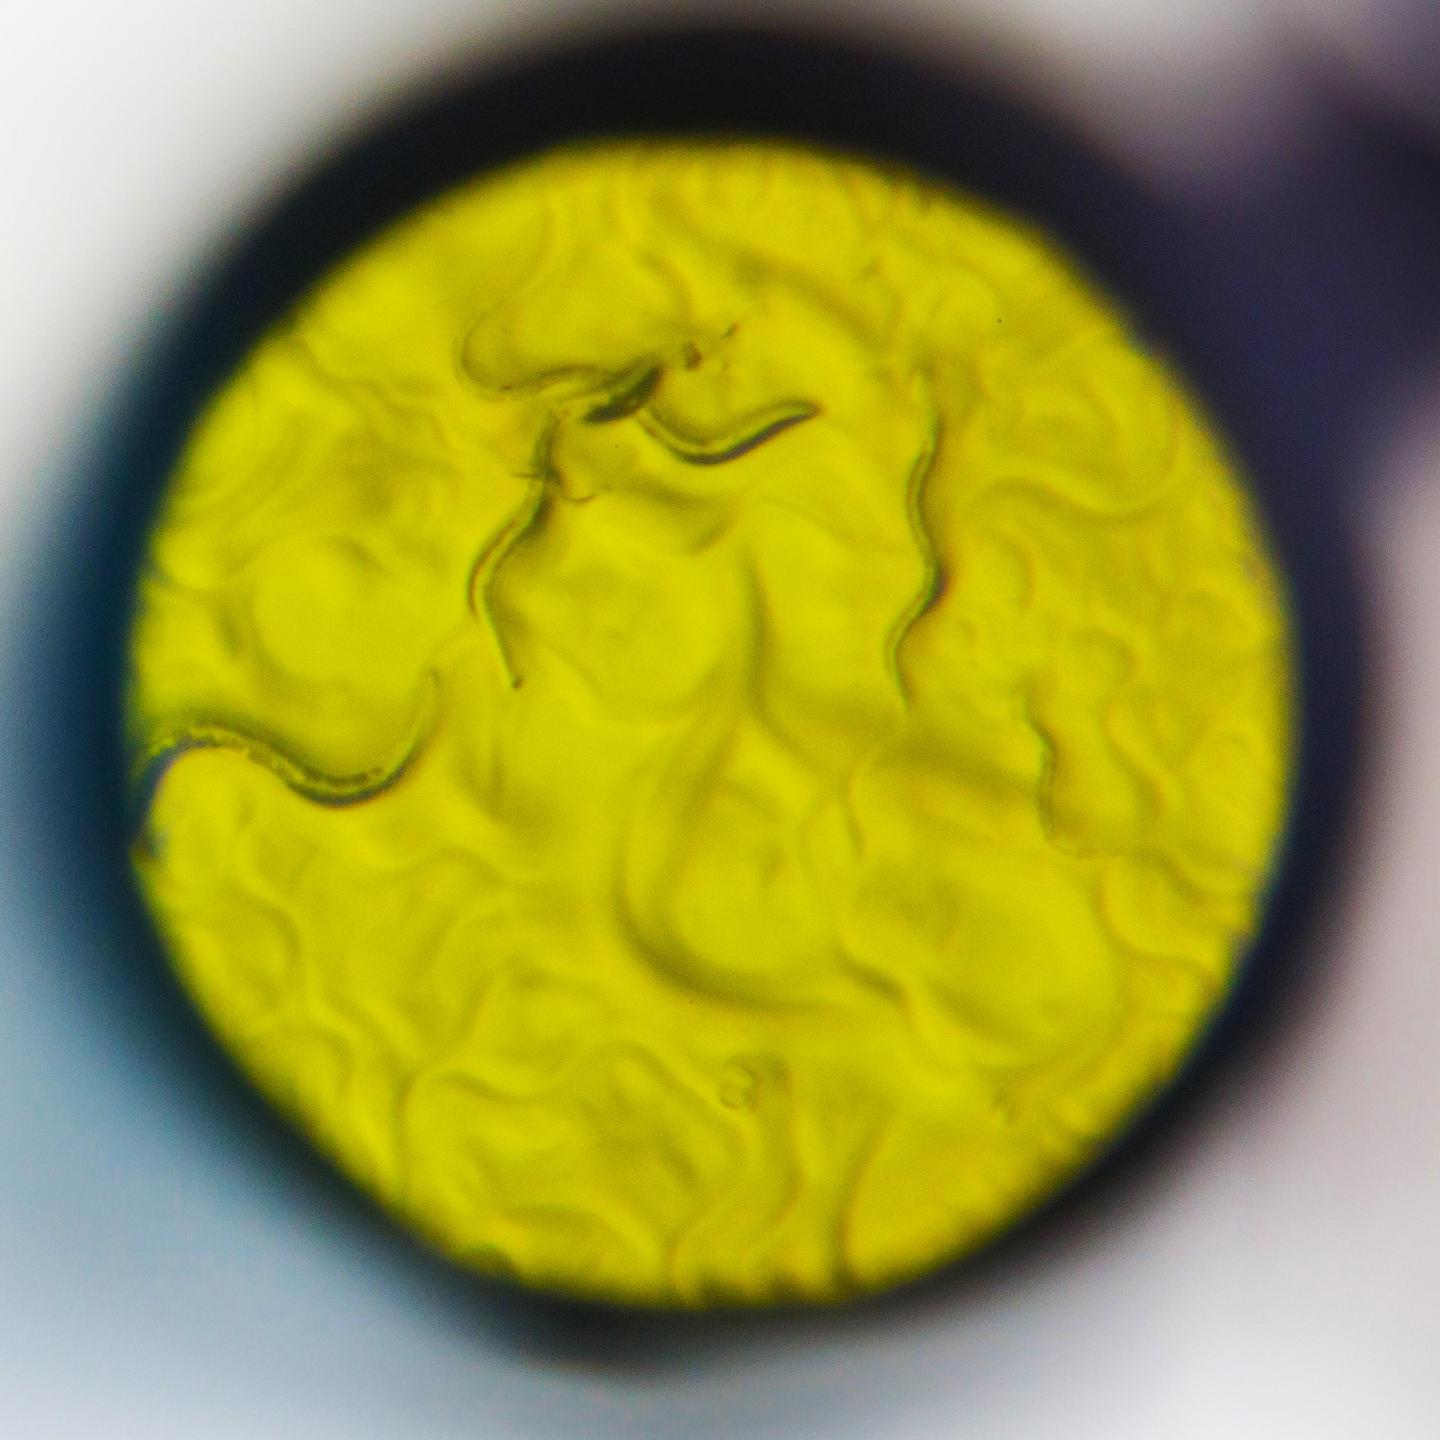

image: The nematode worm C. elegans is commonly used by neuroscientists to understand the nervous system. Scientists at Scripps Research in Florida used it in a new way to discover fresh insights about how cells regulate opioid signaling.

Scott Wiseman for Scripps Research

They used a small soil dwelling animal, the nematode worm, to discover something surprising about one of the most-studied drug receptors.

Their system relies upon the nematode c. elegans, engineered to express the mammalian surface receptor for painkilling drugs, the μ (mu) opioid receptor (MOR). The receptor is not normally found in the worms' DNA, and adding it made the transgenic animals respond to opioids like morphine and fentanyl. The researchers then exposed the worms to mutagens and selected the ones with abnormal responses to opioids. Whole-genome sequencing and CRISPR engineering was then used to pinpoint the genes responsible for those aberrant responses.